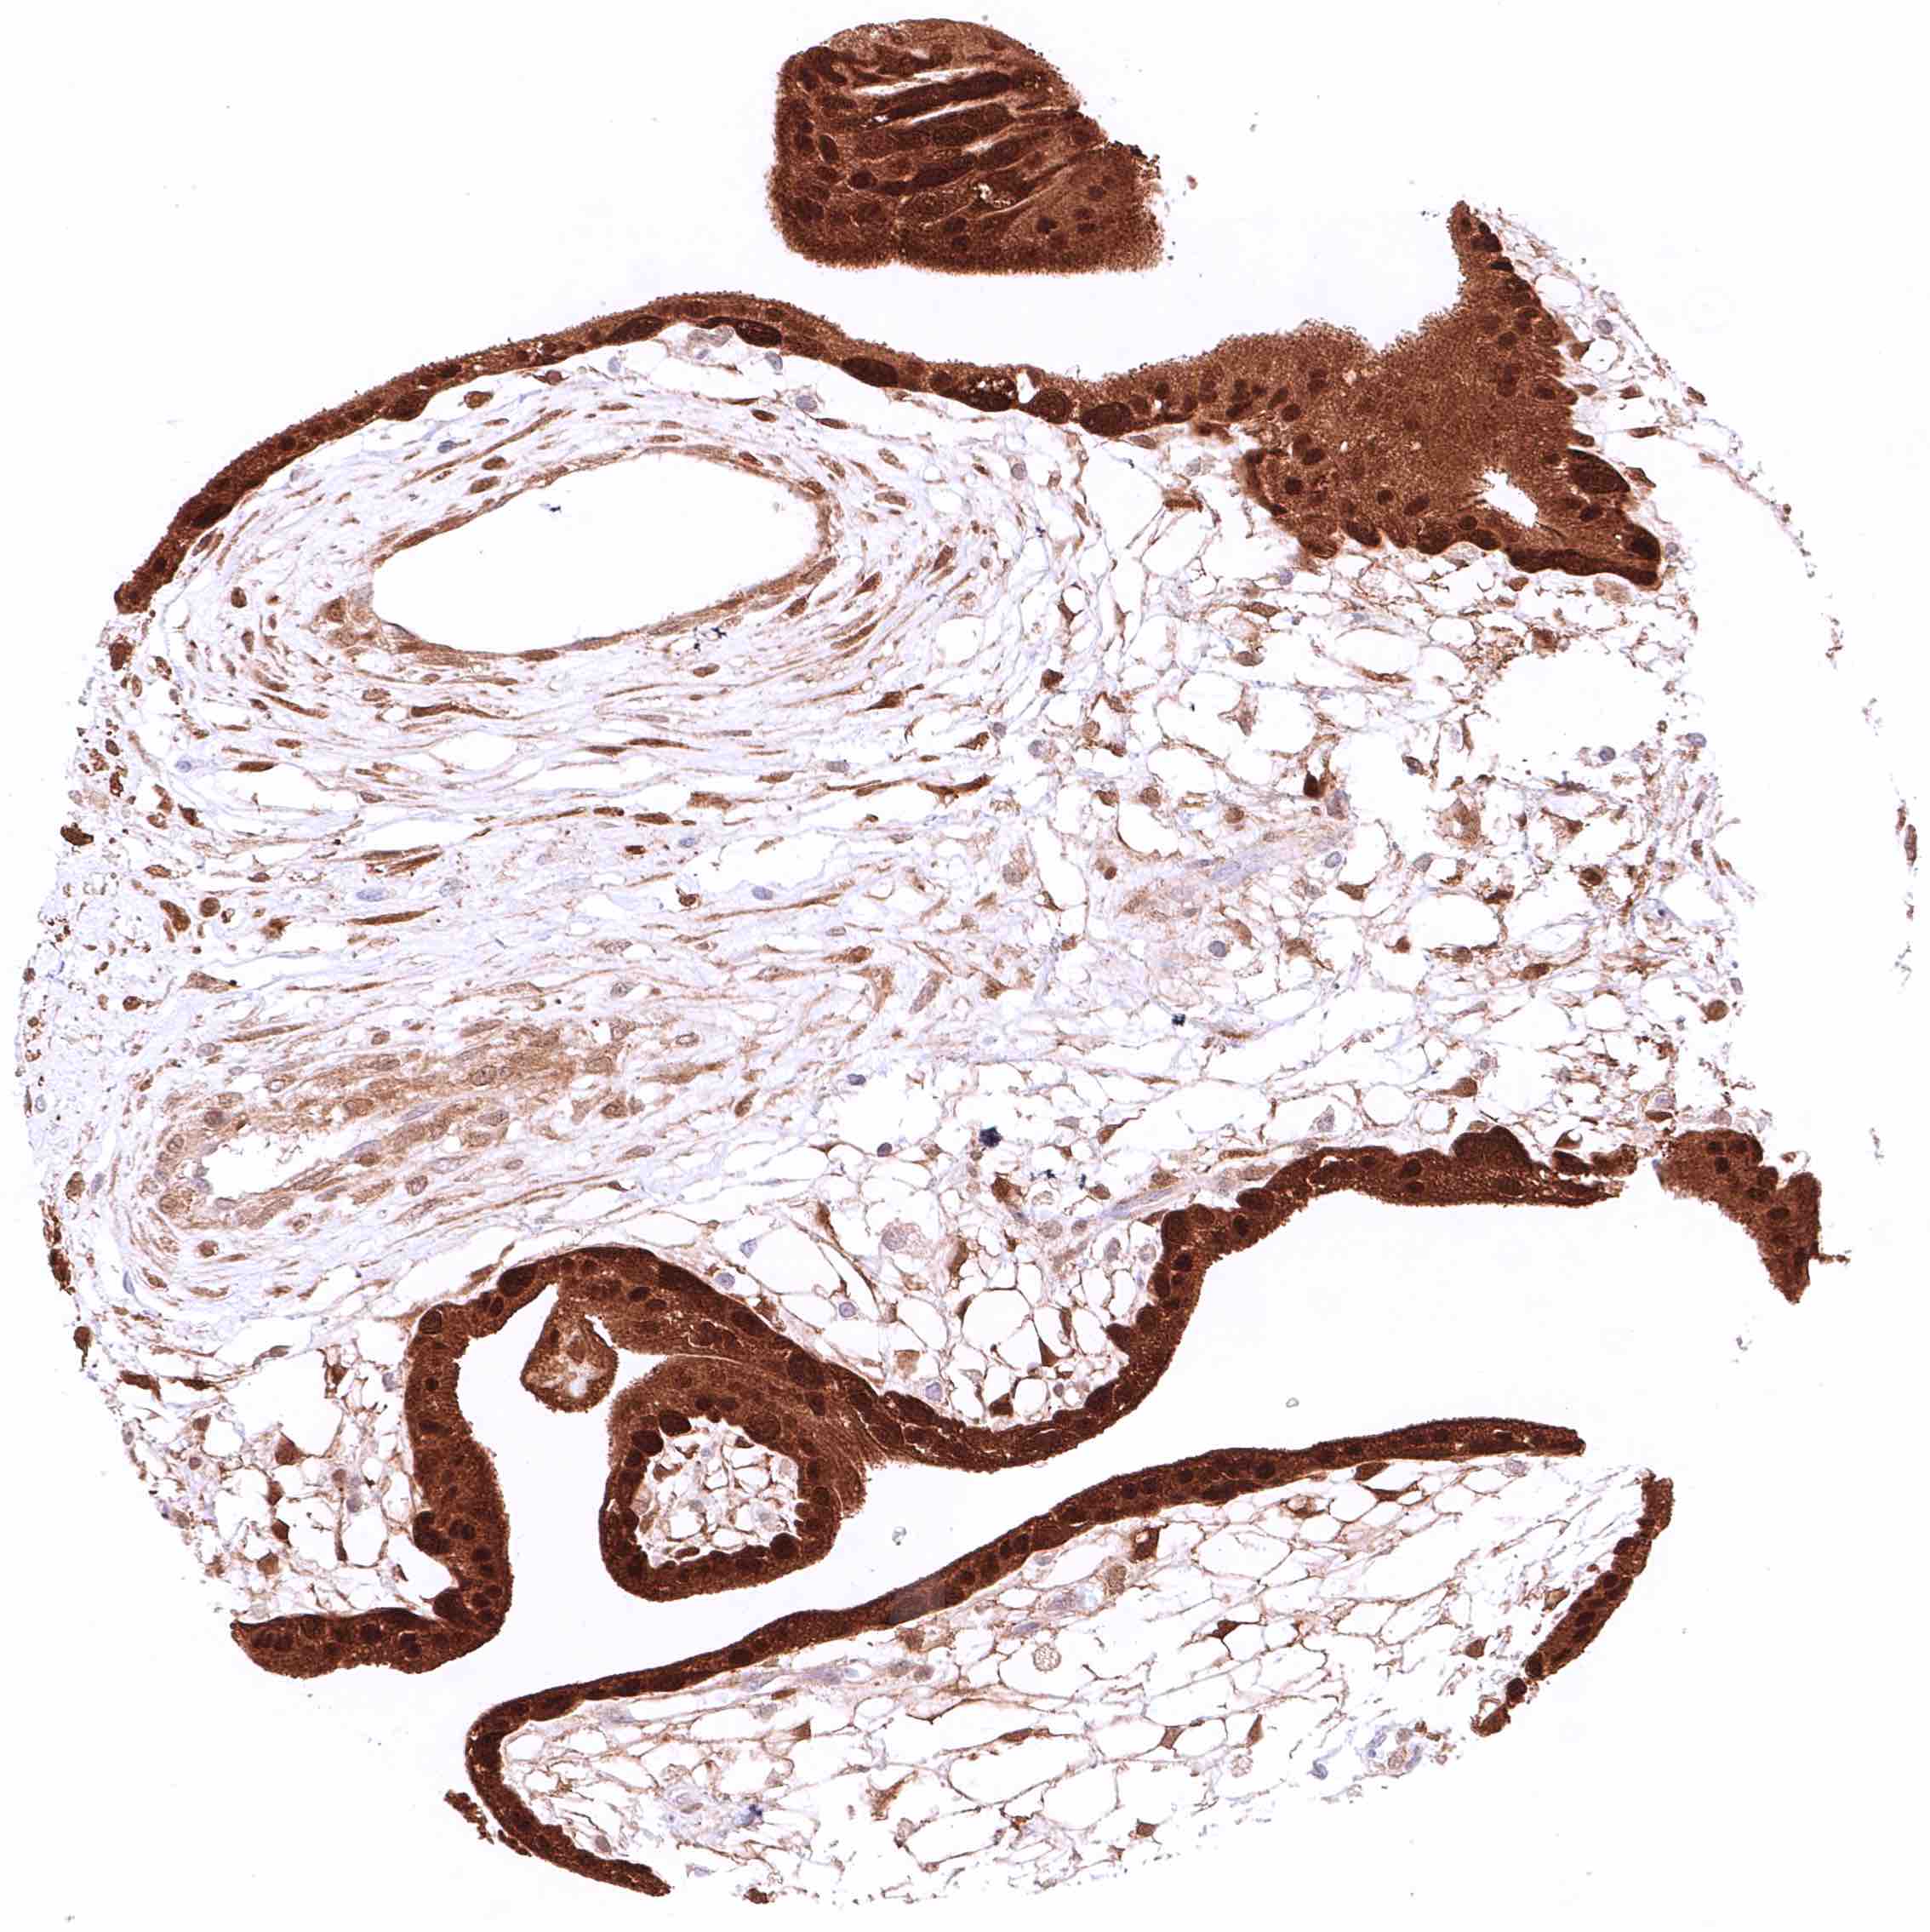

Uterus, ectocervix – Cytoplasmic and nuclear GSTP1 positivity of variable intensity of squamous epithelial cells. Staining intensity is highest in the basal and suprabasal cell layers and decreases towards the surface